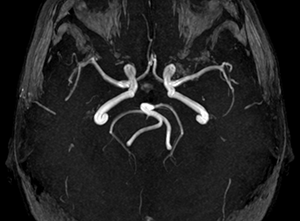

Диагноз той или иной аномалии развития Виллизиева круга можно установить только с привлечением современных инструментальных методов обследования. Возможности в диагностике дали шанс специалистам проанализировать характер распространенности вариантов в строении сосудов мозга и их разновидности, но еще относительно недавно выводы можно было делать в основном по результатам вскрытий умерших больных.

Разработка методик ультразвуковой допплерографии и магнитнорезонансной томографии позволили сделать исследование характера строения Виллизиева круга общедоступным и безопасным мероприятием. К основным способам диагностики вариантов сосудистой системы мозга относят:

- Рентгеноконтрастную ангиографию — один из наиболее информативных методов, но имеет противопоказания, связанные с необходимостью контрастирования (патология печени, почек, аллергия на контраст и др.);

- Транскраниальную допплерографию — процедура безопасна, доступна по цене, требует наличия аппаратов с допплеровским датчиком, которые есть во многих медицинских учреждениях;

- МР-ангиографию — проводится на магнитном томографе, имеет противопоказания, существенный недостаток — дороговизна.

Виллизиев круг на диагностическом снимке

Селективная ангиография сосудов мозга относится к инвазивным процедурам, когда в бедренную артерию вводится катетер, продвигающийся к интересующей зоне церебральных артерий. При достижении необходимой области подается контрастное вещество. Метод применяется чаще всего в ходе оперативного лечения (стентирование, ангиопластика).

Вместо селективной ангиографии может быть применена КТ-ангиография, когда внутривенно вводится контрастное вещество, а затем делаются снимки головы в разных проекциях и срезах. Впоследствии можно воссоздать трехмерное изображение сосудистых структур мозга.

Транскраниальная допплерография позволяет определить характер кровотока в сосудах мозга (снижен, отсутствует), но данных относительно анатомического строения она артерий дает недостаточно. Важным преимуществом ее считают практически полное отсутствие противопоказаний и дешевизну.

МР-ангиография — один из наиболее дорогостоящих, но, вместе с тем, и довольно информативный способ диагностики строения Виллизиева круга. Она проводится в магнитном томографе и противопоказания к ней такие же, как для обычной МРТ (высокая степень ожирения, клаустрофобия, наличие в организме металлических имплантов, проводящих магнитное поле).

МР-картина показывает строение сосудов Виллизиева круга, наличие или отсутствие соединений между ними, аплазию или гипоплазию артерий. При оценке результата специалист может определить диаметр каждой артерии и особенности ее ветвления.

Видео: пример МР-ангиографии мозга

(Виллизиев круг замкнут; определяется извитой S-образный ход интракраниального отдела левой позвоночной артерии; С-образный ход основной артерии; в остальном, в сегментах ВСА и парных артерий кольца основания мозга данных за наличие гемодинамически значимых стенозов, патологических извитостей не получено).

Как видно, каждый из методов имеет и преимущества, и недостатки, поэтому для получения точных выводов касательно артерий мозга их сочетают. Комплексный подход позволяет определить и анатомию сосудов, и характер и направление кровотока по ним, что очень важно в оценке степени риска сосудистых катастроф и возможного прогноза.